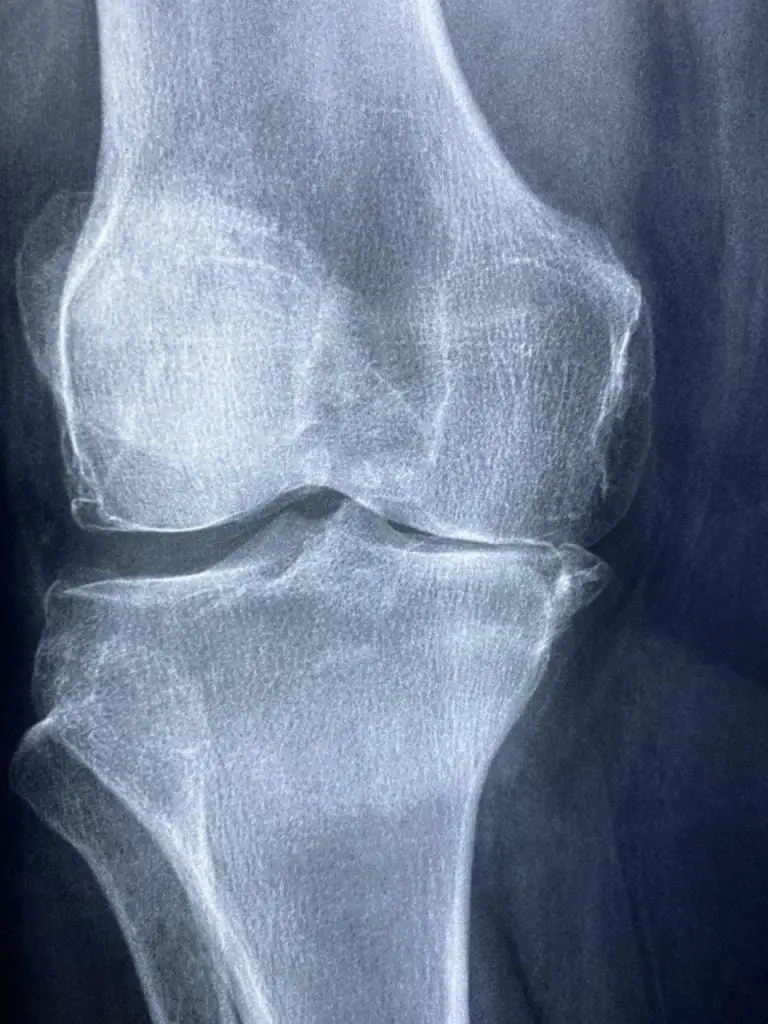

Tijdens een consultatie zal de orthopedist een uitgebreide medische geschiedenis verzamelen en een lichamelijk onderzoek uitvoeren om de aard en oorzaak van de symptomen te beoordelen. Dit kan het uitvoeren van specifieke orthopedische tests omvatten om de mobiliteit, kracht en stabiliteit van het aangedane gebied te evalueren. Aanvullende diagnostische tests, zoals röntgenfoto’s, MRI-scans of echografie, kunnen worden besteld om de diagnose te bevestigen en de ernst van het letsel te beoordelen.